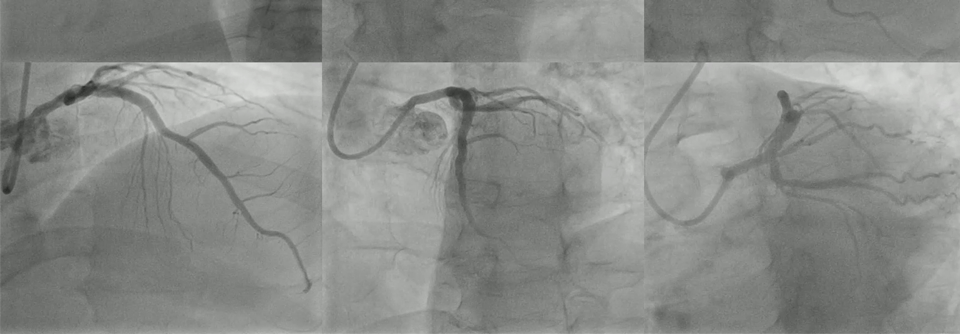

Stark verkalkte Koronarstenosen

Orbitale Atherektomie schlägt Ballonangioplastie nicht

Die orbitale Atherektomie sollte bei schwer kalzifizierten Läsionen das Ergebnis nach Stentimplantation verbessern. In der ECLIPSE-Studie gelang dies…